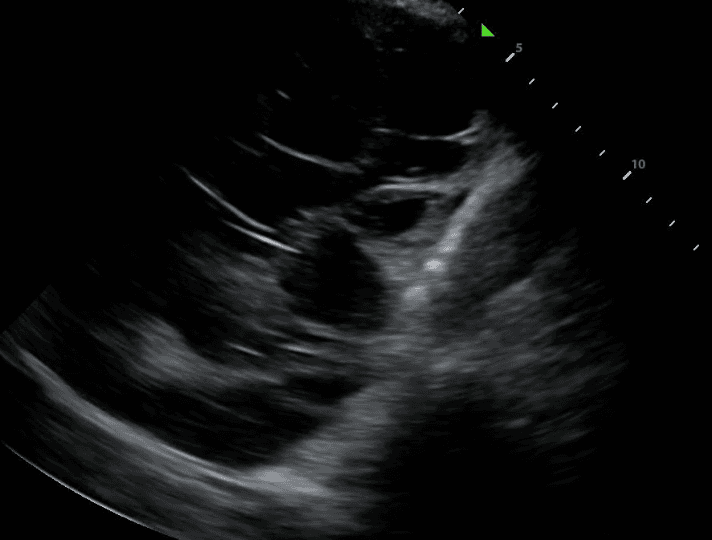

TB can lead to the accumulation of fluid in the pleural space, resulting in a pleural effusion. The incidence of these effusions range from 3% to 30% depending on the prevalence of TB and comorbidities such as HIV. On lung ultrasound, pleural effusion typically appears as anechoic (black) or hypoechoic (dark) fluid collection between the lung and the chest wall. The presence of pleural effusion in TB may indicate complications such as pleural TB or concurrent bacterial infection.

Lung ultrasound will also demonstrate diseased lungs that are filled with fluid or cellular debris. Lung consolidations often have bright air bronchograms, which represent air trapped in fluid filled bronchi.